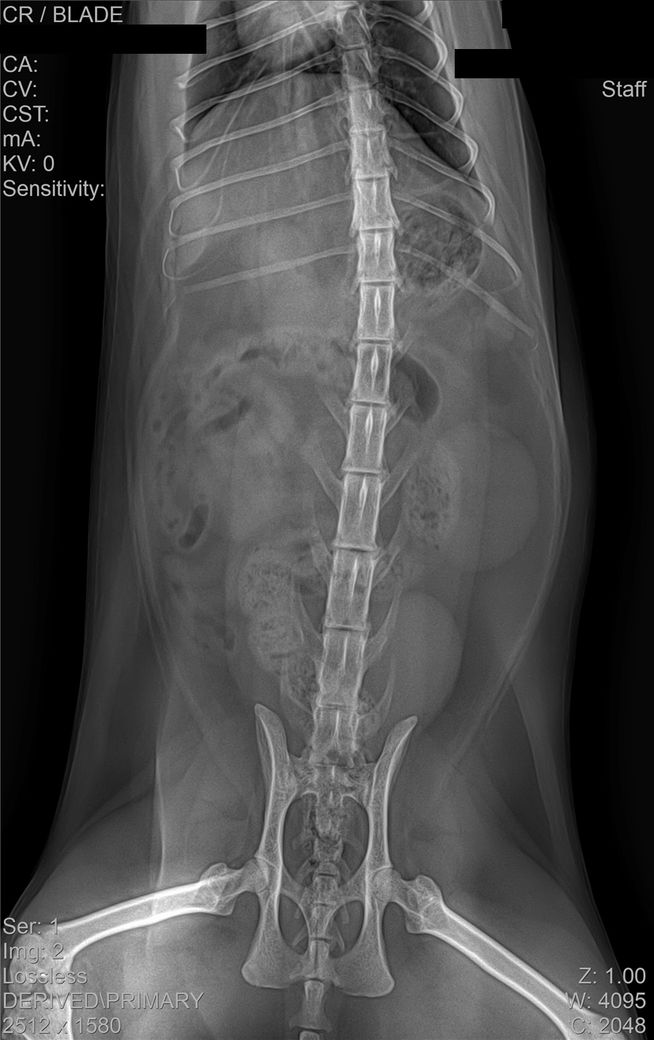

건강검진 때 받은 사진입니다

건강검진 받은 병원에서는 따로 소견을 주지 않으셨으나 지인이 이 사진을 보고

자신의 첫째 고양이가 진단 받았었던 HCM과 엑스레이 사진이 유사하다는 말을 들어서요

HCM의 경우 방사선 상으로는 완전히 진단하는 것이 어렵습니다.

진단을 하려면 영상전문 수의사로부터 심장초음파 소견을 듣는 것이 정확합니다.

HCM이 심할 경우 심장 모양이 valentine shape으로 보이기도 합니다. 아무래도 수의사 선생님이 이런 양상으로 HCM 가능성을 말씀하신 듯하니 심장초음파 진료가 가능한 병원 가셔서 검사 해보시기 바랍니다.

HCM의 진단의 golden standard 는 심장초음파 검사입니다. 하지만 첨부된 자료에는 심장 초음파 검사 결과가 없고

흉부 방사선 검사 또한 외측상이 결여되어 있어 자료로 판단할 수 없습니다.

주치의에게 요청하여 심장 초음파 검사를 진행해 보시기 바랍니다.